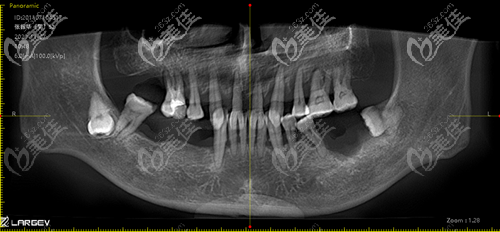

陳先生術(shù)前口內(nèi)照

就診前陳先生拍的CT,難看出全口沒(méi)剩幾顆好牙了,牙齒松動(dòng)明顯、殘根斷齒,多顆牙缺失,年無(wú)法正常咀嚼,真的非常痛苦,所以針對(duì)他的情況選擇全口種植效果會(huì)更好。